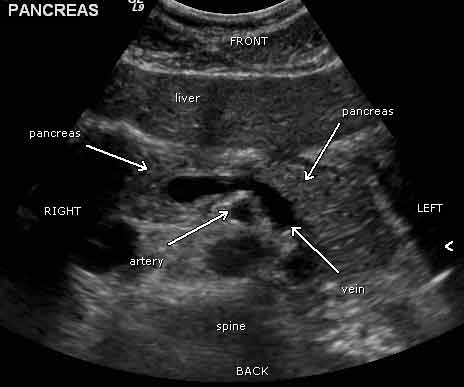

Páncreas normal en un ultrasonido. Vista desde el abdomen hacia la cabeza del paciente. El hígado se encuentra delante del páncreas. Una vena que sale del bazo está detrás del páncreas.

Nota: Las imágenes se muestra para fines ilustrativos. No trate de sacar conclusiones comparando esta imagen con otras en el sitio. Solamente los radiólogos calificados deben interpretar las imágenes.